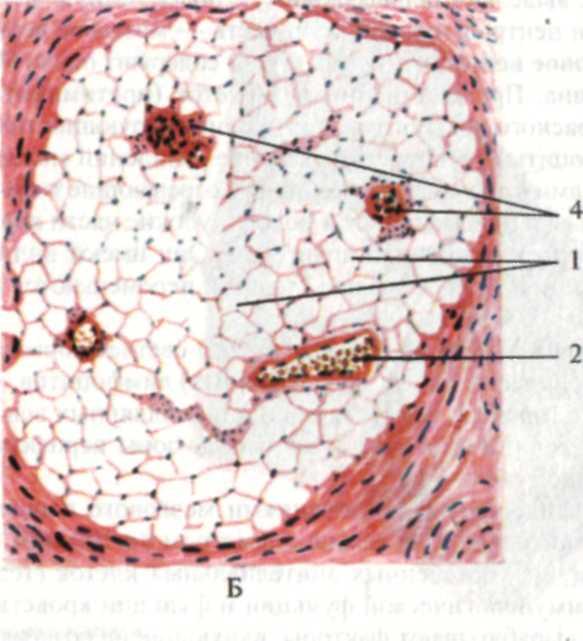

Изучение костного мозга: анатомия и функции